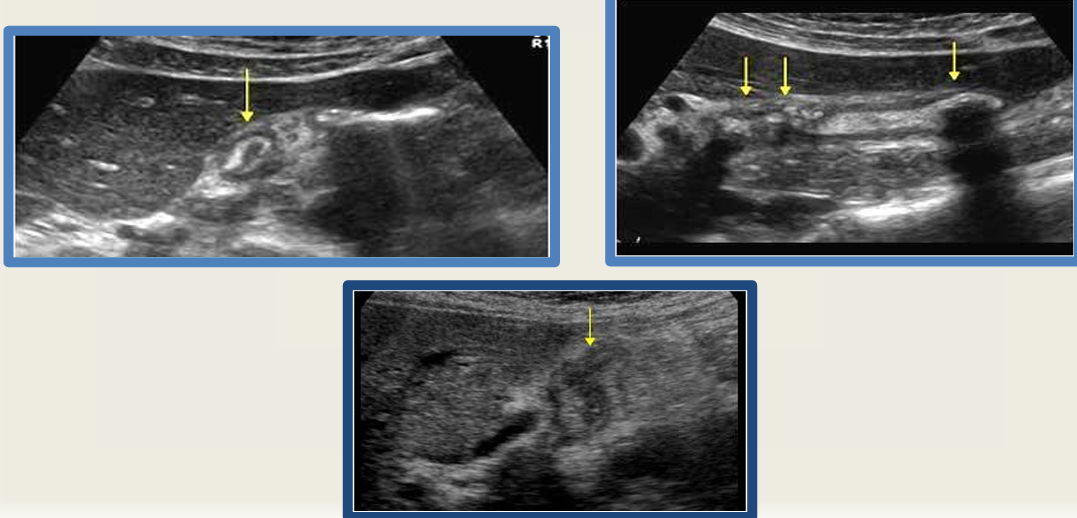

sludge

porcelain GB

gb polyps

adenomyomatosis